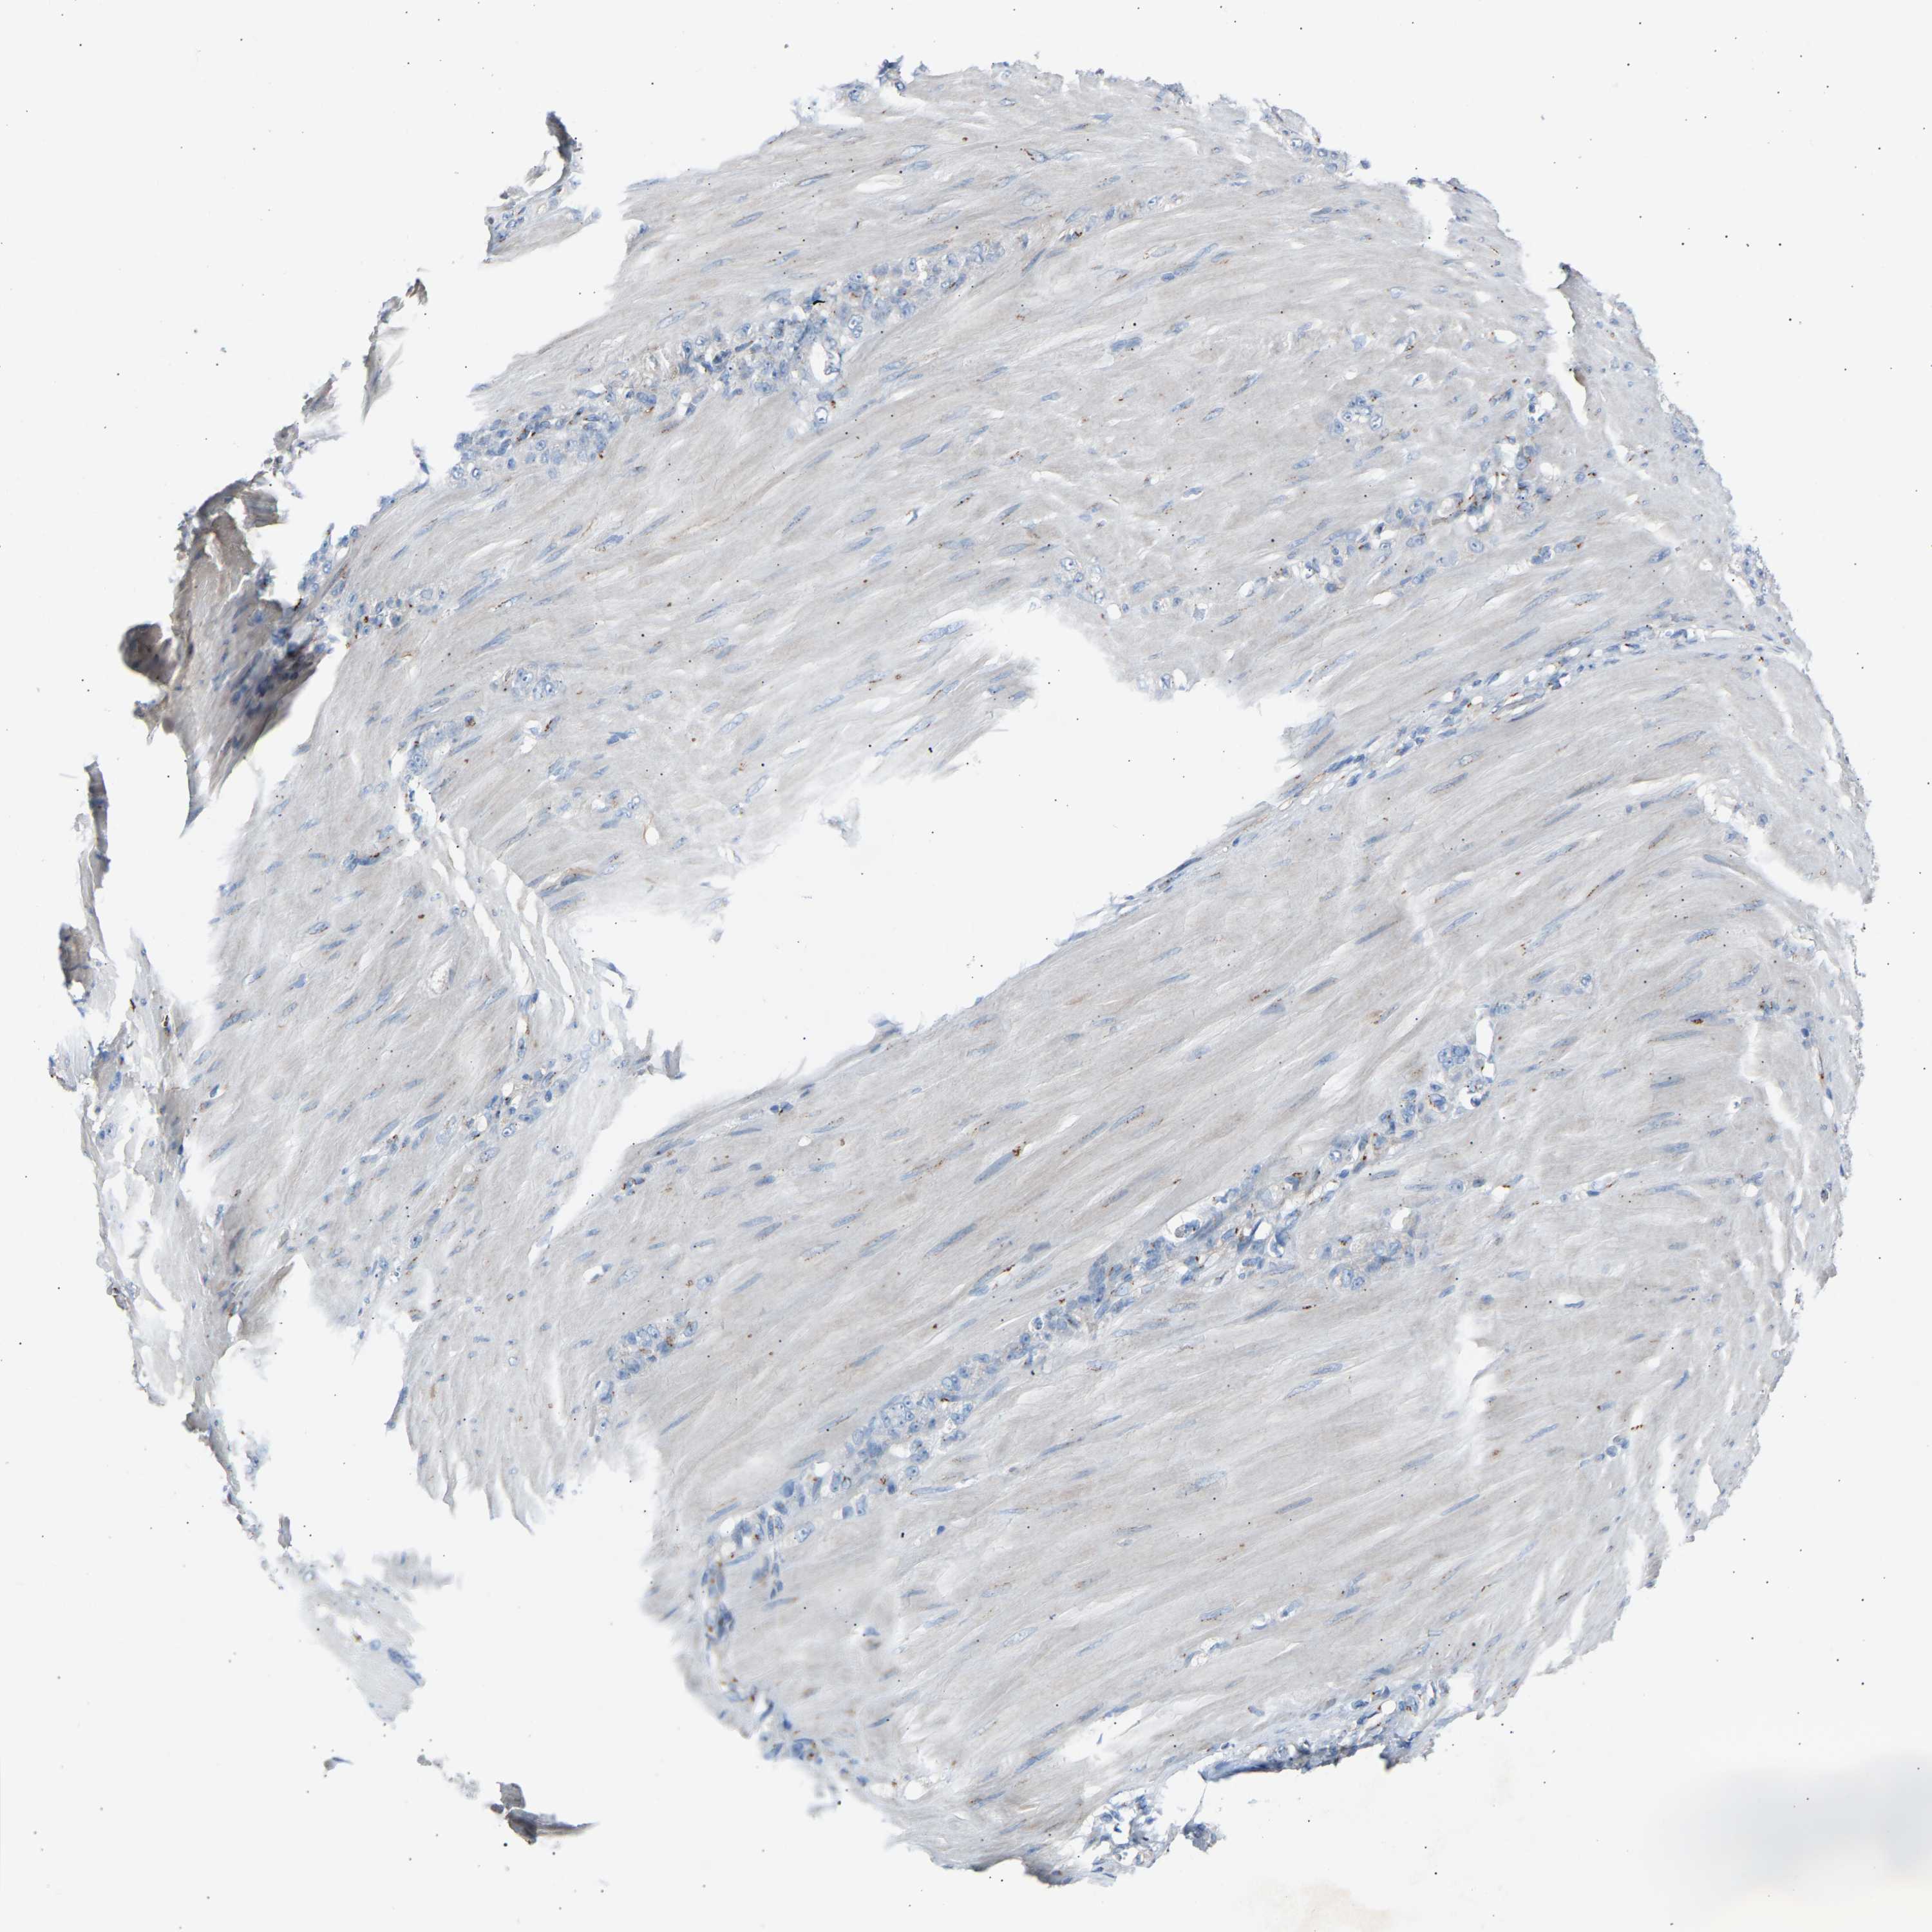

STOMACH CANCER - Protein expressioni

A mouse-over function shows sample information and annotation data. Click on an image to view it in a full screen mode. Samples can be filtered based on level of antibody staining by selecting one or several of the following categories: high, medium, low and not detected. The assay and annotation is described here.

Antibody stainingi

Antibody staining in the annotated cell types in the current human tissue is reported as not detected, low, medium, or high, based on conventional immunohistochemistry profiling in selected tissues. This score is based on the combination of the staining intensity and fraction of stained cells.

Each image is clickable and will lead to virtual microscopy that enables deeper exploration of all samples and also displays staining intensity scores, fraction scores and subcellular localization as well as patient and tissue information for each sample.

Antibody HPA020060

Staining

High

Medium

Low

Not detected

Intensity

Strong

Moderate

Weak

Negative

Quantity

>75%

75%-25%

<25%

None

Location

Nuclear

Cytoplasmic/membranous

Cytoplasmic/membranous,nuclear

Adenocarcinoma, NOS